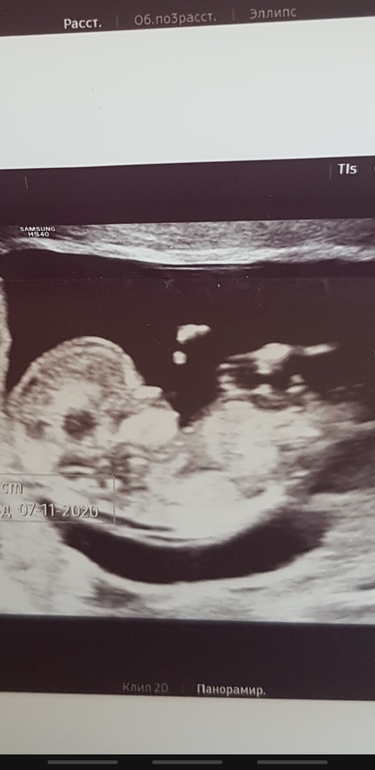

Мальчик или девочка???

На кого похож ?🥰

УЗИ 12 недель 4 дня мальчик или девочка?

На узи сказали 99 % мальчик ',,, хотела бы узнать у кого так была))) спасибо за ранее всем